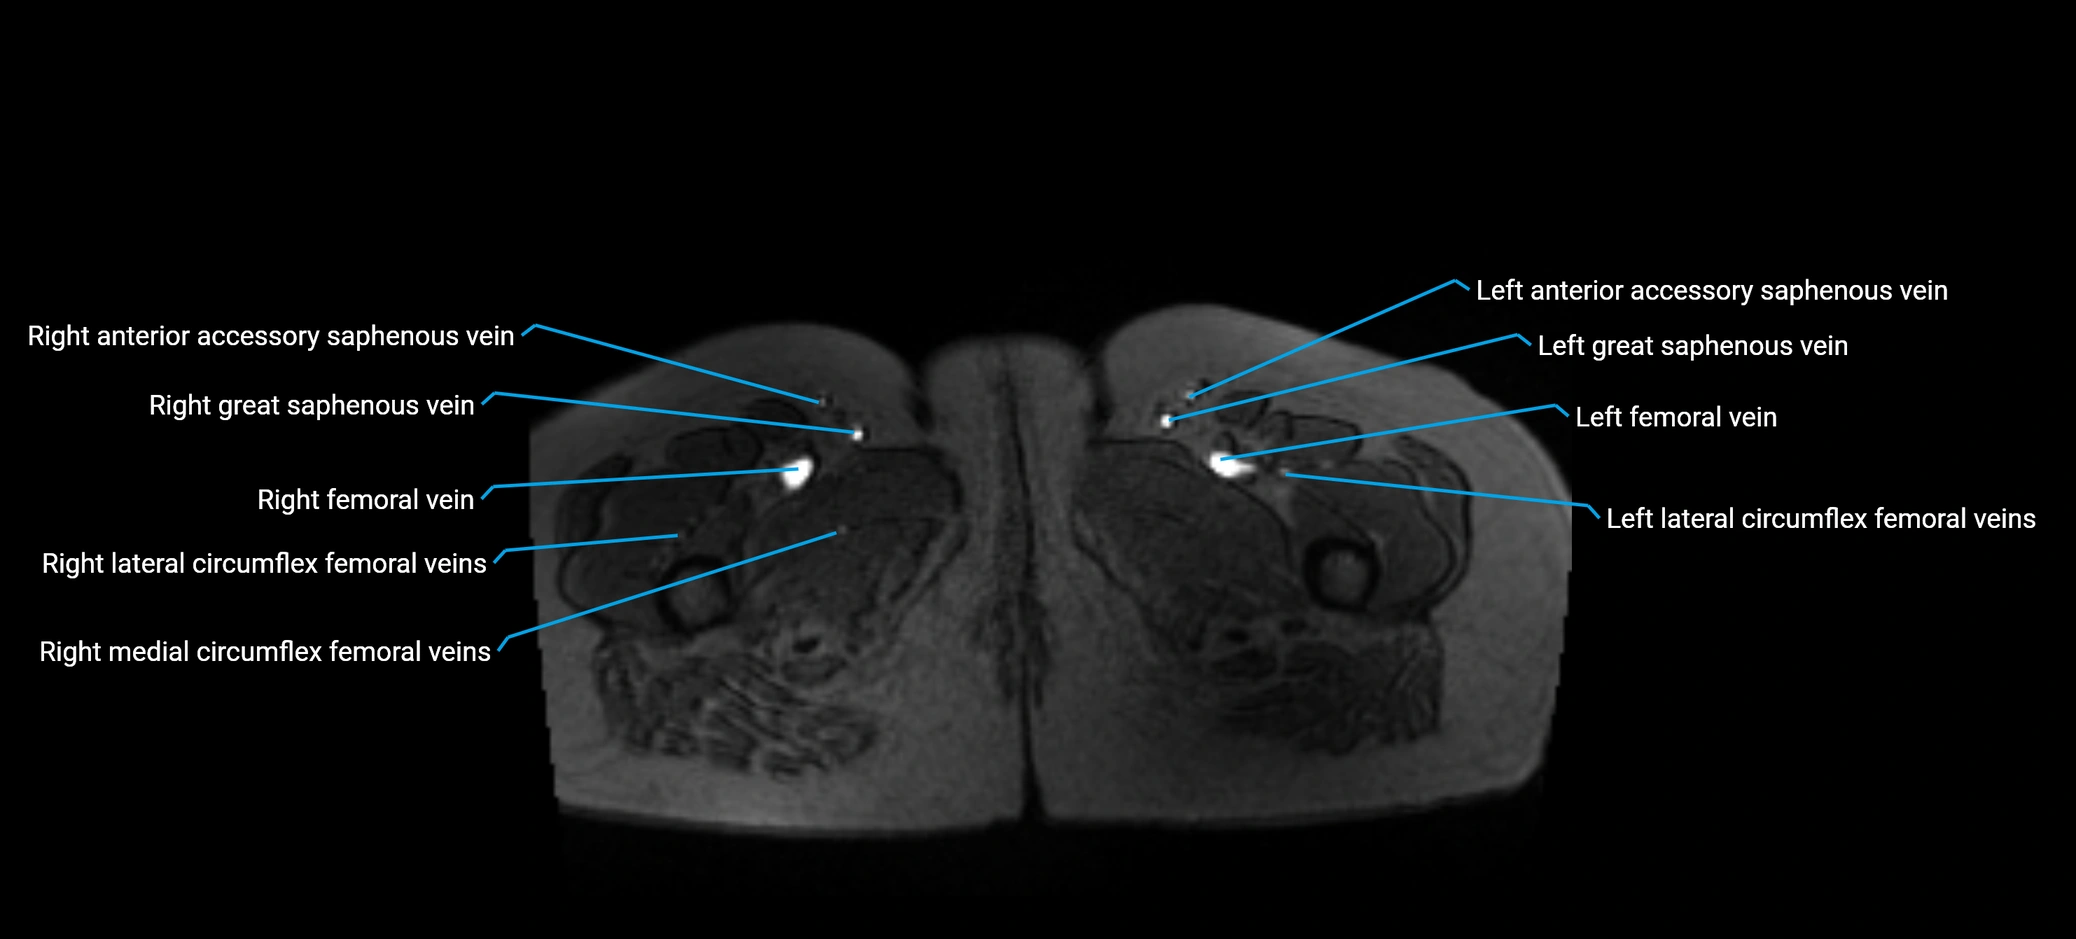

MRI image

image